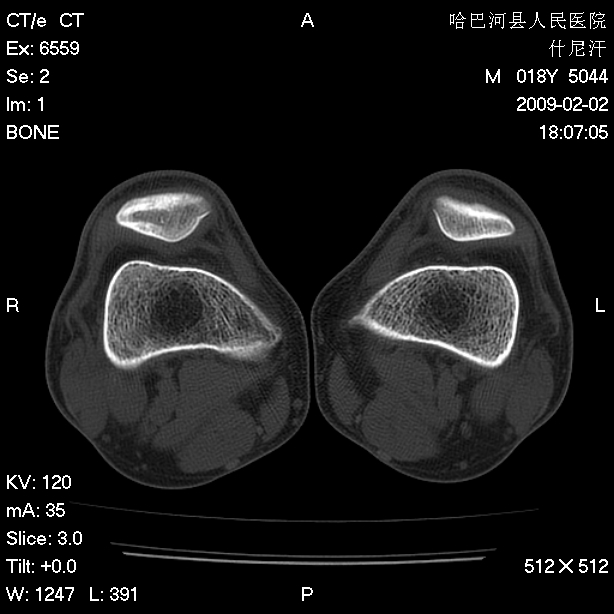

标题: CT17889:外伤后右膝关节反复疼痛3年余 [打印本页]

标题: CT17889:外伤后右膝关节反复疼痛3年余

ct未见明显异常。关节腔未见明显积液,半月板未见明显撕裂。但最好还是mri看看韧带及半月板情况。